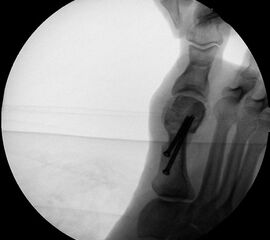

Präoperatives Röntgenbild Fuß d.p. mit eingezeichneten Winkeln. A) Intermetatarsalwinkel, B) Hallux valgus Winkel, C) Interphalangeal-Winkel.

Abbildung 2

• Operationsplanung anhand der Röntgenaufnahmen unter Beachtung wichtiger radiologischer Landmarks wie Intermetatarsalwinkel, Hallux valgus – Winkel, distaler Gelenkflächenwinkel (Distal Metatarsal Articular Angulation - DMAA), Metatarsaleindex und Sesambeinposition (Abb. 2).